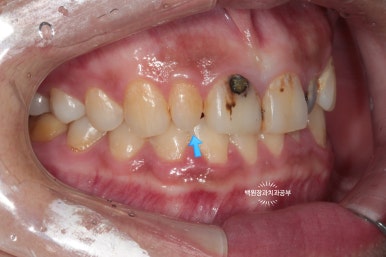

고개를 살짝 돌려 찍어본 사진에서 더 확연히 치아우식증( =충치)을 확인 할 수 있습니다.

딱 보기에도 치료가 아주 시급해 보이는 상황이었어요!!

그리고 화살표로 표시한 양쪽 작은 앞니는 왜소치로 그 크기가 2/3 정도로 작은 소견을 보실 수 있습니다.